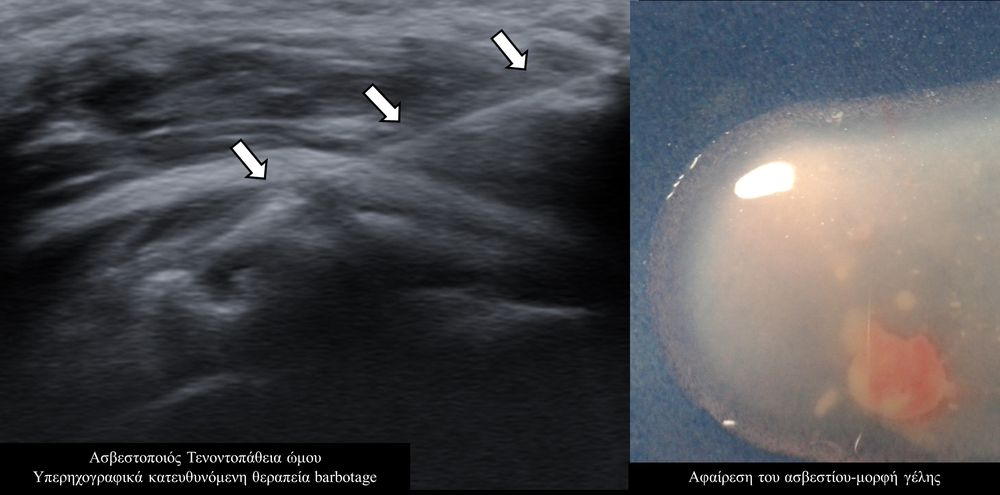

Η υπερηχογραφικά καθοδηγούμενη αφαίρεση των επασβεστώσεων (barbotage) είναι μια ελάχιστα παρεμβατική (minimally invasive) τεχνική θεραπείας για την ασβεστοποιό τενοντοπάθεια. Με τους υπερήχους είναι δυνατός ο εντοπισμός των ασβεστώσεων και η διαδερμική τοποθέτηση μιας βελόνας στο κέντρο της συμπτωματικής ασβέστωσης. Στη συνέχεια γίνεται διαδερμικός τρυπανισμός και επαναλαμβανόμενες πλύσεις του ασβεστίου, με αποτέλεσμα τόσο την αφαίρεση της παθολογικής επασβέστωσης όσο και την αυξηση τοπικά της αιμάτωσης με αποτελεσμα την σταδιακή απομάκρυνση των παραγόντων φλεγμονής-ερεθισμού.